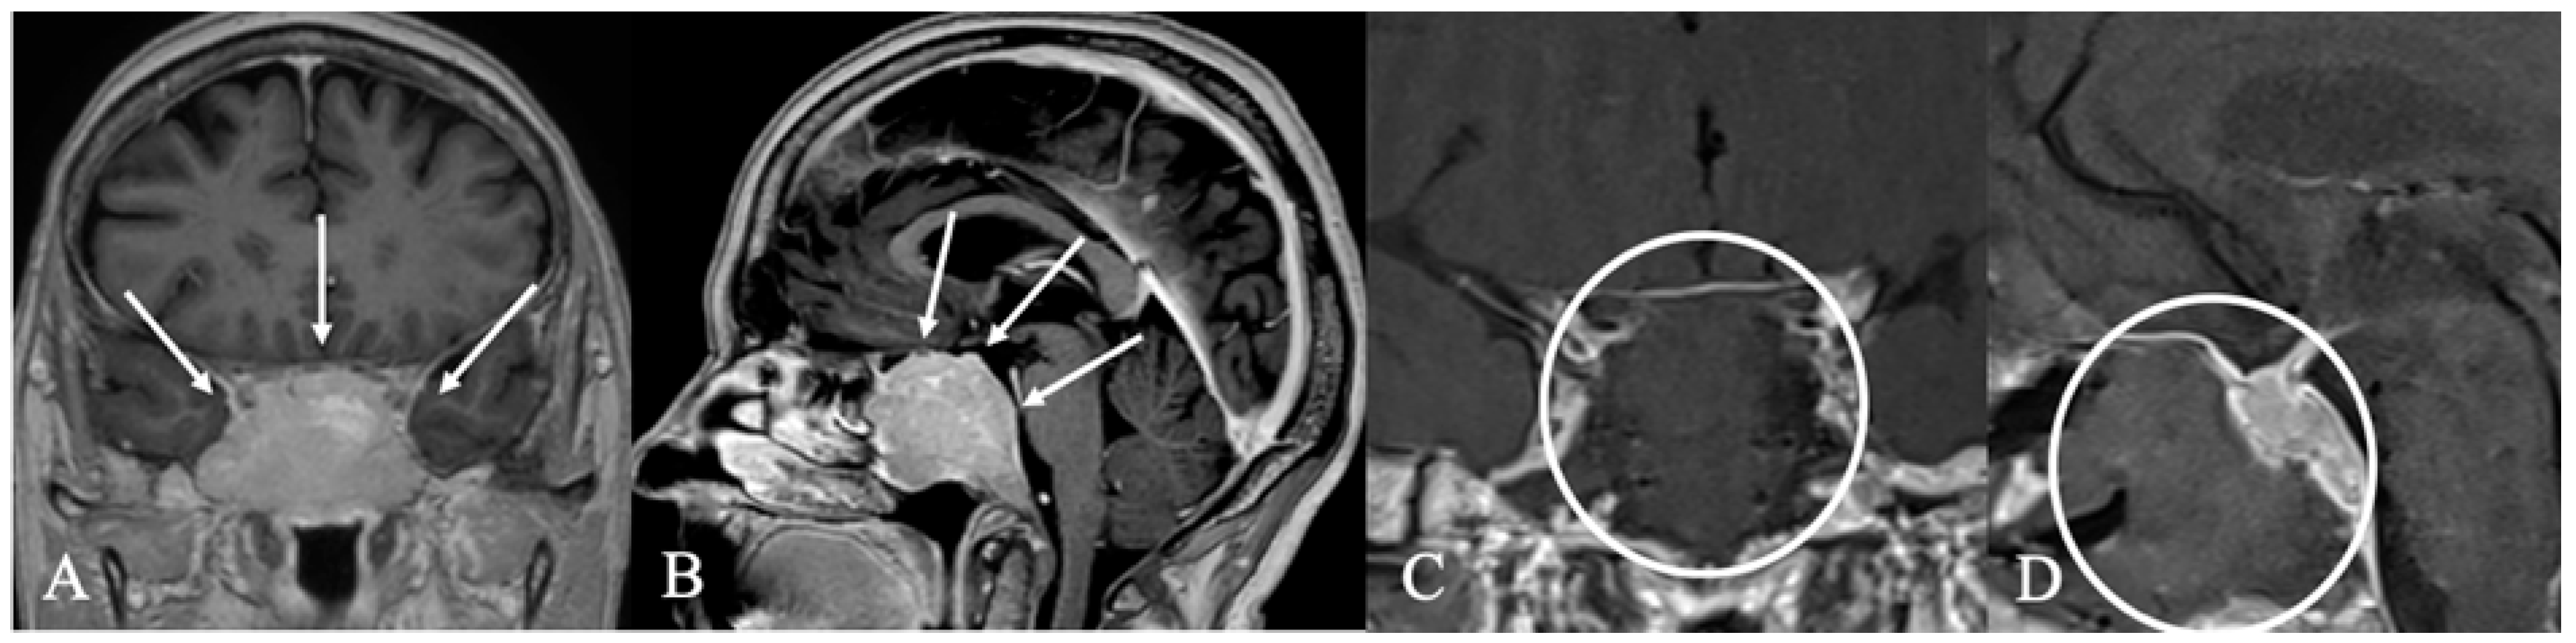

4.2. Differential Diagnoses and Case Presentations